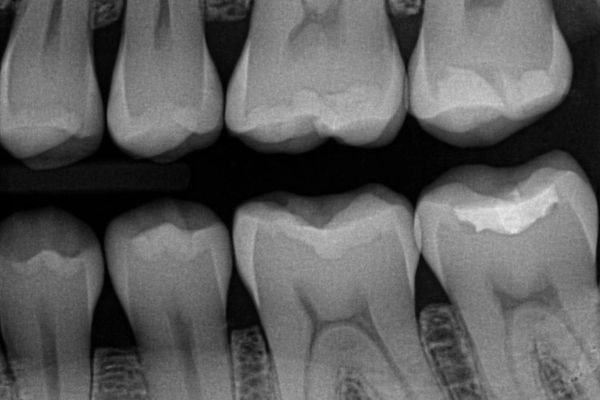

Digital dental x-rays are an essential tool for diagnosing and monitoring your oral health. Instead of traditional film, digital x-rays use an electronic sensor to capture highly detailed images instantly. This allows your dentist to detect cavities, evaluate bone levels, check for infections, and plan treatments with exceptional accuracy — all while keeping your visit quick and comfortable.

• Instant, high-resolution images

Because the images appear immediately on-screen, your dentist can review them with you right away. Digital files also provide better clarity and can be enhanced (zoomed, brightened, contrasted) to identify issues earlier.